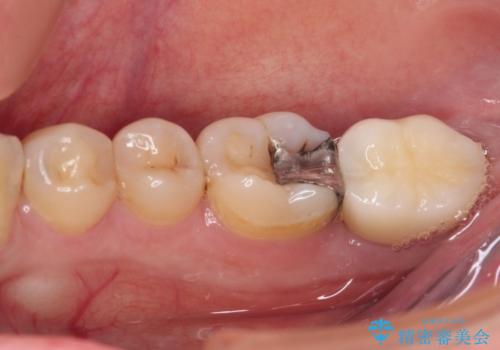

- 右上下の奥歯がむし歯でしみたり痛んだりするとのことで来院された患者様です。

下顎の奥歯は強い痛みを感じており、既に歯髄に不可逆的な炎症が起きていると診断されたため、根管治療の後にセラミッククラウンにて補綴治療を行うこととしました。

上顎の奥歯は最近銀歯による治療を行ったとのことでしたが、適合が不十分であり隙間からしみていたため、適合の良いゴールドインレーにて修復治療を行うこととしました。

下顎のむし歯は歯肉の中にまで及んでいたため、一部歯槽骨を削除し、歯肉縁上に健全歯質が位置するよう外科処置を併用しました。